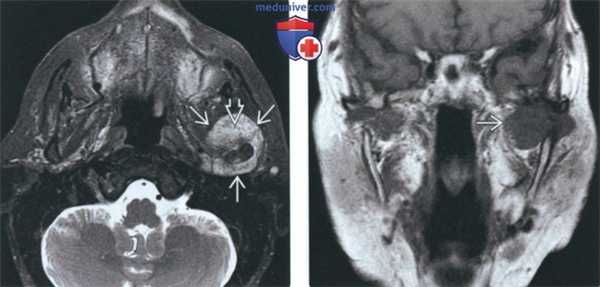

(Слева) На аксиальной КТ правого ВНЧС в коаном окне спереди ог мыщелка визуализируются «грубые» обызвеавления. Кортикальная пластинка мыщелка интактна, наружный полюс склерозирован вследавие дегенеративных изменений.

(Справа) На панорамном изображении правого ВНЧС визуализируется мыщелок обычных размеров и формы. Спереди и сзади от мыщелка определяется неоднородное затемнение. Объемное образование имеет большие размеры и приводит к рааяжению суаавной капсулы.

3. КТ при первичном синовиальном хондроматозе ВНЧС:

• КТ в костном окне:

о Множественные обызвествленные/оссифицированные узлы вокруг мыщелка нижней челюсти

о Часто обнаруживаются дегенеративные изменения суставной поверхности мыщелка:

- Неровный контур, склероз

о Расширение суставного пространства

о Может обнаруживаться отек мягких тканей или объемное образование смешанной плотности, солидная часть которого отражает метаплазию синовиальной ткани

о Сообщается об интракраниальном распространении

(Слева) На аксиальной КТ у этого же пациента вдоль внутреннего, наружного, переднего края мыщелка визуализируются множественные обызвествленные/оссифицированные свободные тела различного размера. Су аавная капсула в значительной степени растянута.

(Справа) На косом корональном срезе (Т1) у этого же пациента в пределах растянутой капсулы визуализируются обызвествленные/оссифицированные свободные тела.

(Слева) На аксиальной КТ в костном окне у пациента с синовиальным хондроматозом левого ВНЧС спереди и снаружи от мыщелка определяется объемное образование с множественными точечными обызвествлениями.

(Справа) На косой сагиттальной MPT(Т2 ВИ) определяется неоднородный сигнал позади мыщелка, сопоставимый с хрящевыми узлами, и обызвествление/оссификация спереди от него.